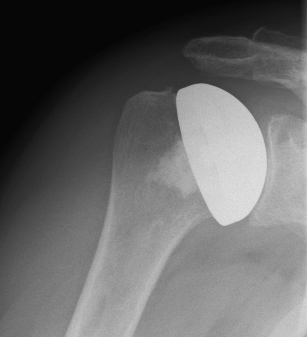

left: X-ray image of an omarthrosis

X-rays can be used to reliably diagnose the extent of joint wear. In the case of severe osteoarthritis, for example, the joint space and the formation of jagged edges (osteophytes) can be detected. If additional damage to the tendons of the shoulder (rotator cuff) is suspected, ultrasound examination (sonography) or magnetic resonance imaging (MRI) can help clarify the situation.

Surface replacement ("cap prosthesis" of the humeral head) in cases of mild omarthrosis and still well-preserved glenoid cavity

links: X-ray image of a cap prosthesis ("surface replacement")

right: cap prosthesis ("surface replacement", type "Durom" Fa. Zimmer)gkl